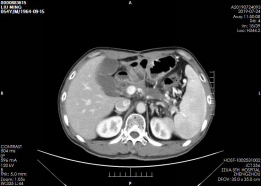

患者入院后李晓勇教授全面评估病情,结合患者病史及CT检查,患者为胰腺颈部恶性肿瘤(图1)。考虑到胰腺肿瘤位置复杂包裹大血管,并且已向周围组织浸润转移,无法行根治性手术切除。面对棘手问题,李晓勇教授积极组织全科会诊,共同探讨治疗方案,射频微波并发症凶险,放疗化疗不敏感,可考虑行一种全新的肿瘤消融治疗技术——纳米刀消融治疗。该技术通过释放高压电脉冲在肿瘤细胞膜上形成纳米级不可逆性穿孔,使细胞快速凋亡,既能达到肿瘤消融凋亡坏死的目的,同时又能保证手术的安全性。

▲ 图一 肿瘤侵犯肝总动脉、脾动脉 浸润脾静脉和门静脉